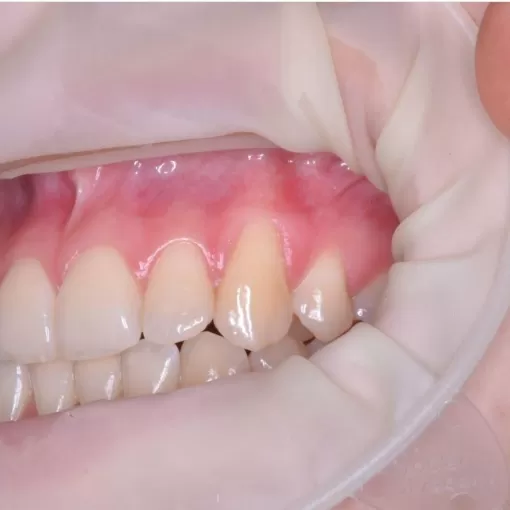

Закрытие рецессии десны в 2 этапа в области 4.1 зуба после ортодонтического лечения

Стоматолог-хирург Патеюк А.Л.

Закрытие рецессии десны в 2 этапа в области 4.1 зуба после ортодонтического лечения. Туннельная методика с подсадкой собственных тканей пациента.